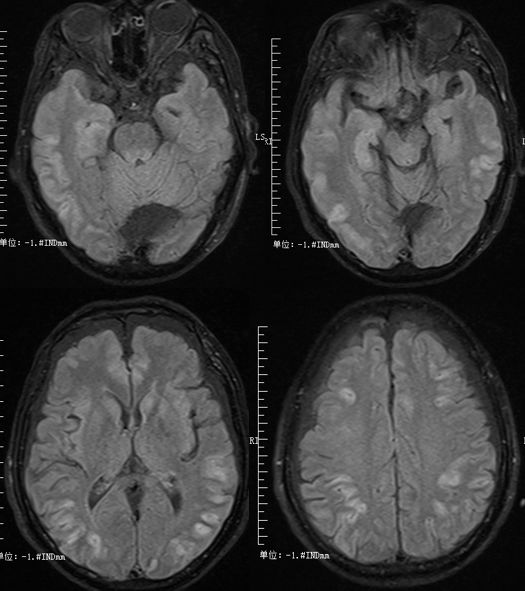

男性18岁,发热、恶心、呕吐3天。(补充:自行口服甲硝唑1.2g/d 后出现共济失调、眩晕。)

答案: 甲硝唑相关脑病(Metronidazole-induced encephalopathy MIE)。

本周一的晨读病例都是良心病例,难度程度均不高。特征性影像表现剑指甲硝唑和山豆根。甲硝唑的神经毒性主要包括前庭小脑系统损害、自主神经损害、视神经损害、周围神经损害及癫痫发作等。甲硝唑引起的CNS损害多具有可逆性,及时停药后,临床症状可短期内改善。MIE的MRI改变:典型病变区域在小脑齿状核、中脑、脑桥被盖、延髓背侧及胼胝体压部,通常双侧对称受累。小脑齿状核和中脑下丘对称性病灶被认为是MIE的特征性表现。MIE鉴别诊断:中枢神经系统脱髓鞘疾病及其他代谢性和中毒性脑病。其中,Wernicke脑病最需与MIE鉴别。WE特征MRI表现:第三、四脑室旁、导水管周围、乳头体、四叠体、丘脑对称性病灶。